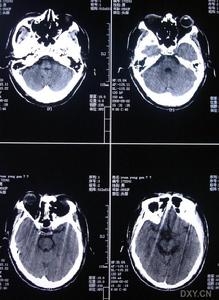

中青年人既往有高血壓、糖尿病、心臟病血液病或感染病史等,出現神經系統定位體徵如偏癱、失語等局灶性神經功能障礙,或其他腦局灶性症狀,一般無明顯的意識障礙應考慮腦梗死的可能需及時做腦CT掃描或腦MRI檢查有助於確診。

其它輔助檢查:包括CT、MRI、ECG心臟超聲、顱外及經顱超聲無其他卒中危險因素而有栓塞史者,需進一步作血管造影檢查如有皮膚異常或懷疑罕見動脈病者,可做皮膚活檢。